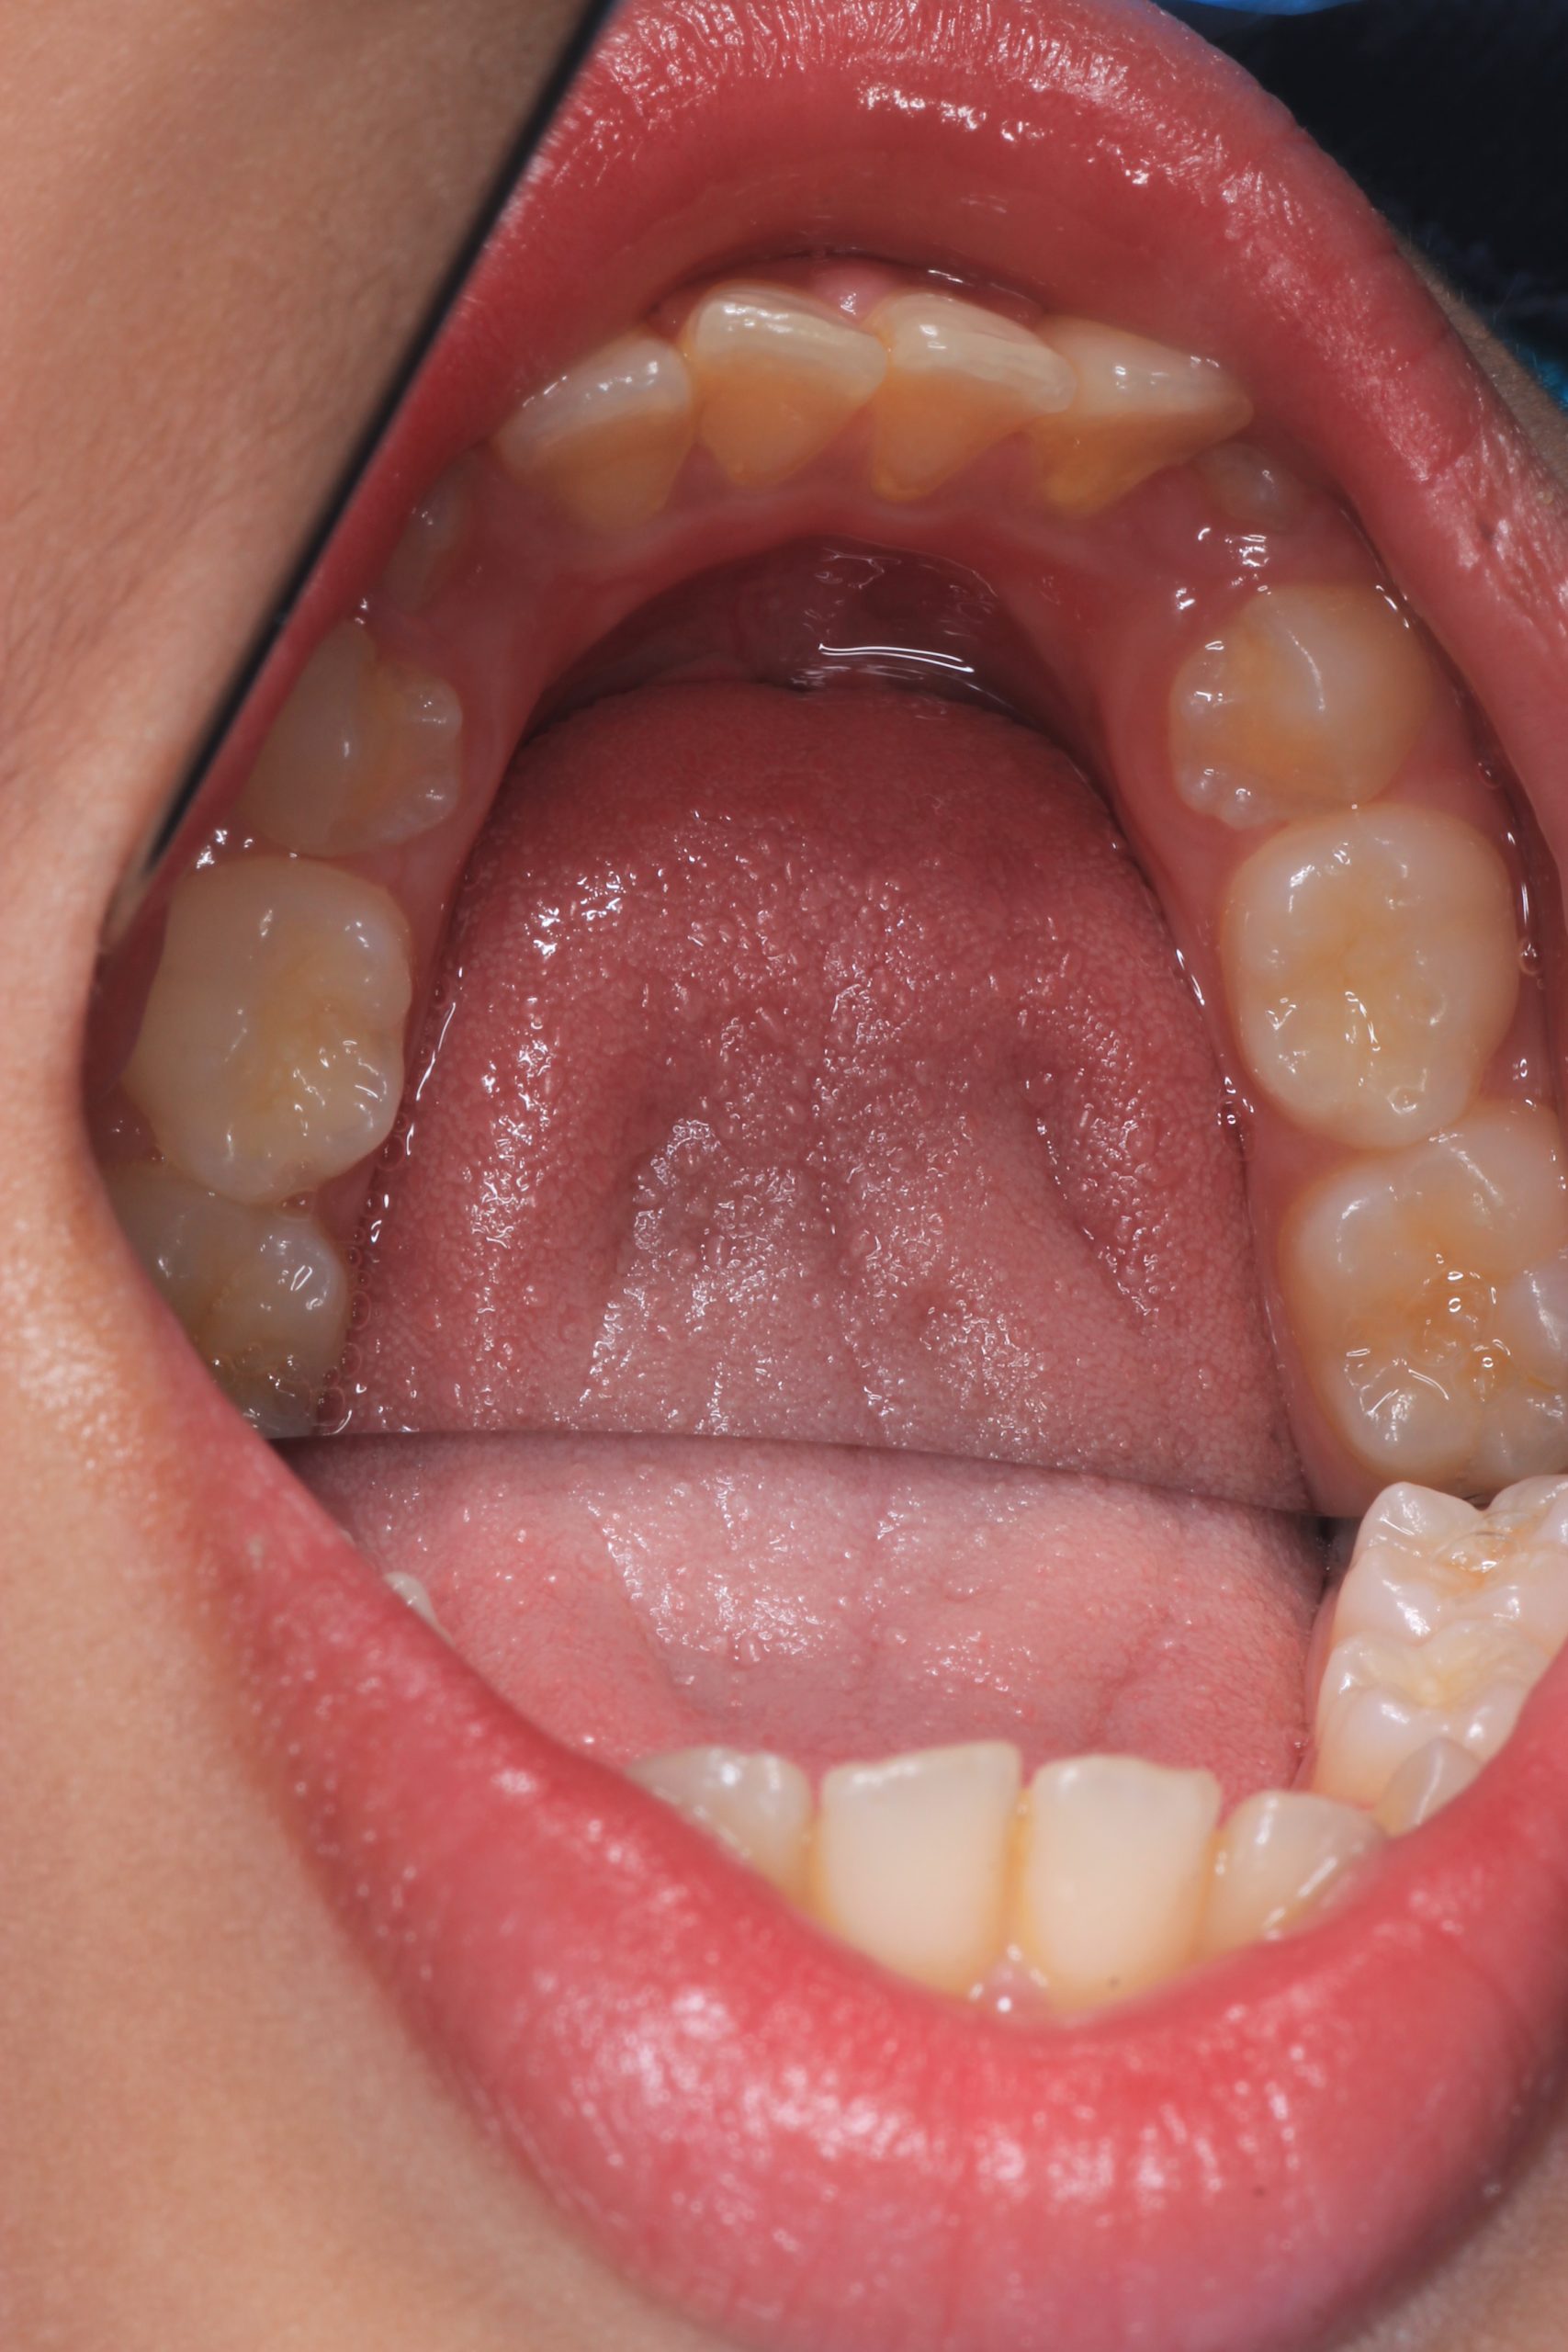

We examine the condition of teeth, gums, and bite. - Plaque Disclosure with Special Indicators

Areas that weren’t cleaned well appear purple. The darker the shade, the older the plaque. This helps both kids and parents understand where brushing needs to improve. - Brushing Training & Home Care Tools Selection